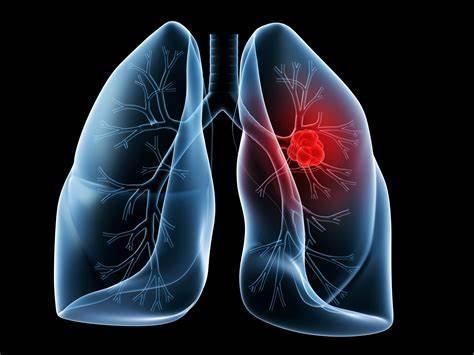

肺癌普查的主要手段美国国家癌症中心,建议对年龄在55~70岁、每年吸烟超过30包的高危人群,进行低辐射剂量的肺部螺旋CT检查,以筛查肺癌。这些人群中,往往能够发现一些明确的肺癌患者。但在检查过程中,也发现有一些人并没有明显的肺癌迹象,只查出了“孤立性”的肺结节。

什么是孤立性肺结节?孤立性的肺结节,是指被肺实质完全包围的单发小病灶,直径通常≤3cm,边界通常是清楚的。这些患者通常无症状,也没有伴随肺门淋巴结肿大、肺不张和胸腔积液等表现。对人群的肺癌筛查研究报告显示,有恶性肿瘤发生高风险的吸烟者,孤立性肺结节的患病率高达50?还有其他的一些流行病学调查显示,在肺部CT上偶然发现肺结节的发生率为30?右。放射学上,通常将测得的直径不超过3cm的病变称为结节,而大于3cm的则称为肿块,结节和肿块的区分很重要。